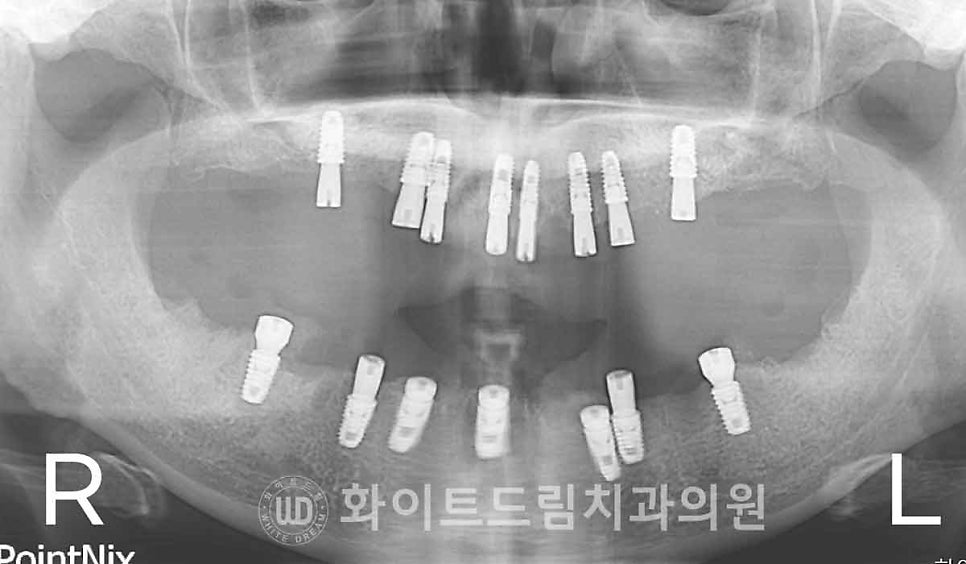

▲ 상악 임플란트 수술일자 : 24.02.17

하악 수술 일자 : 24.03.02

이렇게 총 4회의 내원을 해주신 뒤

골 유착이 진행되는 4개월 후

임플란트 인상채득과정을 위해 한 번 더 내원을 해주시게 됩니다.

임플란트 최종 보철 제작을 위해 구강 스캔을 진행하는 과정이며

다음번 내원으로 최종 보철을 세팅하면 서울전체임플란트는 마무리된답니다.

총 6회의 내원 만으로 전체 임플란트 치료를 마무리하게 되었습니다.